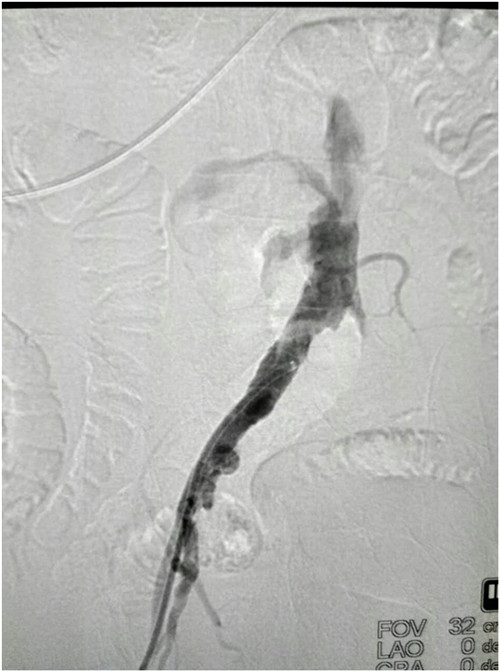

经术前1周精心准备,在科室陈熹主任的统筹协调下,于4月25日下午局麻下在我院介入手术室由普外科马建仓副教授,李宗禹医师在介入室张尚军主管技师配合下完成了普外科首例髂股动脉长段闭塞球囊扩张、支架植入术。术中造影证实左侧髂股动脉闭塞,通过翻山技术从右侧股动脉穿刺入路,导丝顺利通过狭窄病变,球囊扩张后,置入网状支架,使得血管通畅。术后给予双抗,患者静息痛明显改善,换药创面分泌物明显减少,休息明显好转。患者现在正在平稳恢复中。